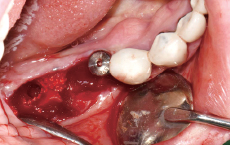

수술 전

#45 Implant 식립

#47 Implant 식립

#45 & #46 부위 골 결손

#45 협측 골이식